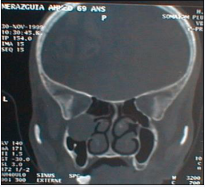

Figure 3 CT axial plane: left maxillary mucocele (posterior part of sinus).

Figure 3: CT axial plane: left maxillary mucocele (posterior part of sinus).

Symptomatology is not specific. We can found nasal obstruction, rhinorrhea, epistaxis, facial pain, facial deformation, proptosis, peri orbital swelling, epiphora, palatal deformity, dental problems or radiologic discovery. Nasal endoscopy shows anomalies of lateral nasal way (disformed). Computed tomography in the axial and coronal plane gives a reliable extension balance, the sinus is enlarged with wall blowed reduced or interrupted. Its contents isodense or hypodense and no contrast enhancement, unless infected.